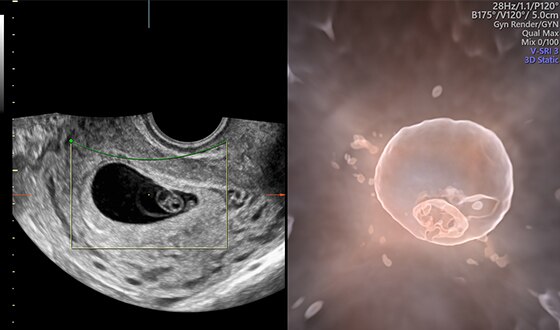

Fetus with HDlive™ generated with SonoRenderlive